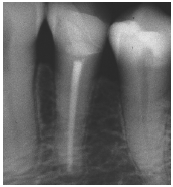

Al momento del examen, 10 (90.9%) EC estaban en función en 10 pacientes. Un molar 26, restaurado con EC, se perdió por enfermedad periodontal después de 12 años y 9 meses en función. Ninguna restauración se desprendió, no hubo recidiva de caries y al examen radiográfico no se observaron lesiones patológicas en los 10 DPET en función (Figs. 1a,1d; 2c; 3c,3d; 4c).

Situación inicial en #26. La raíz distovestibular debe ser amputada.

Preparación dentaria para EC en #26

EC en #26 a los 9 años (Gradia).

Control radiográfico a los 9 años